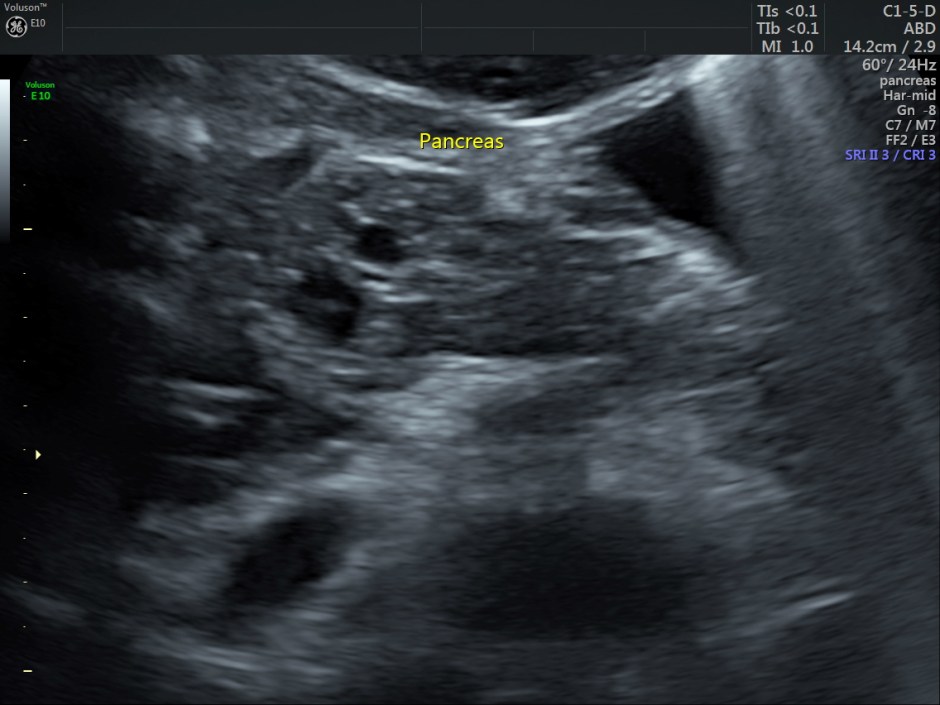

Pancreas also appeared to be normal